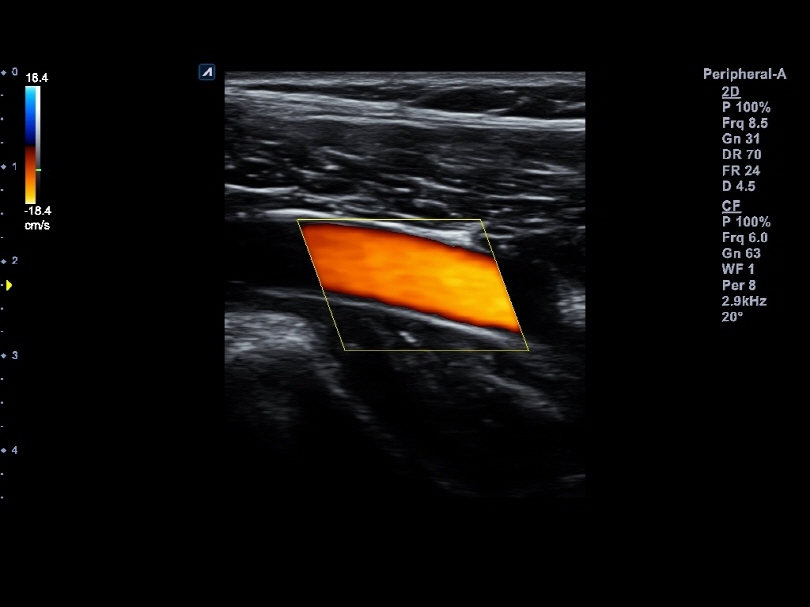

L8-17H

High density linear transducer(8-17MHz)

Application:

Breast, EM, MSK, Vascular, Small Parts

L3-12H

High density linear transducer (3-12MHz)

Application:

Breast, EM, MSK, Vascular, Small Parts

L3-12HWD

High density wide footprint linear transducer (3-12MHz)

Application:

Breast, EM, MSK, Vascular, Small Parts, Appendix

L3-12T

Linear transducer (3-12MHz)

Application:

Breast, EM, MSK, Vascular, Small Parts, Appendix